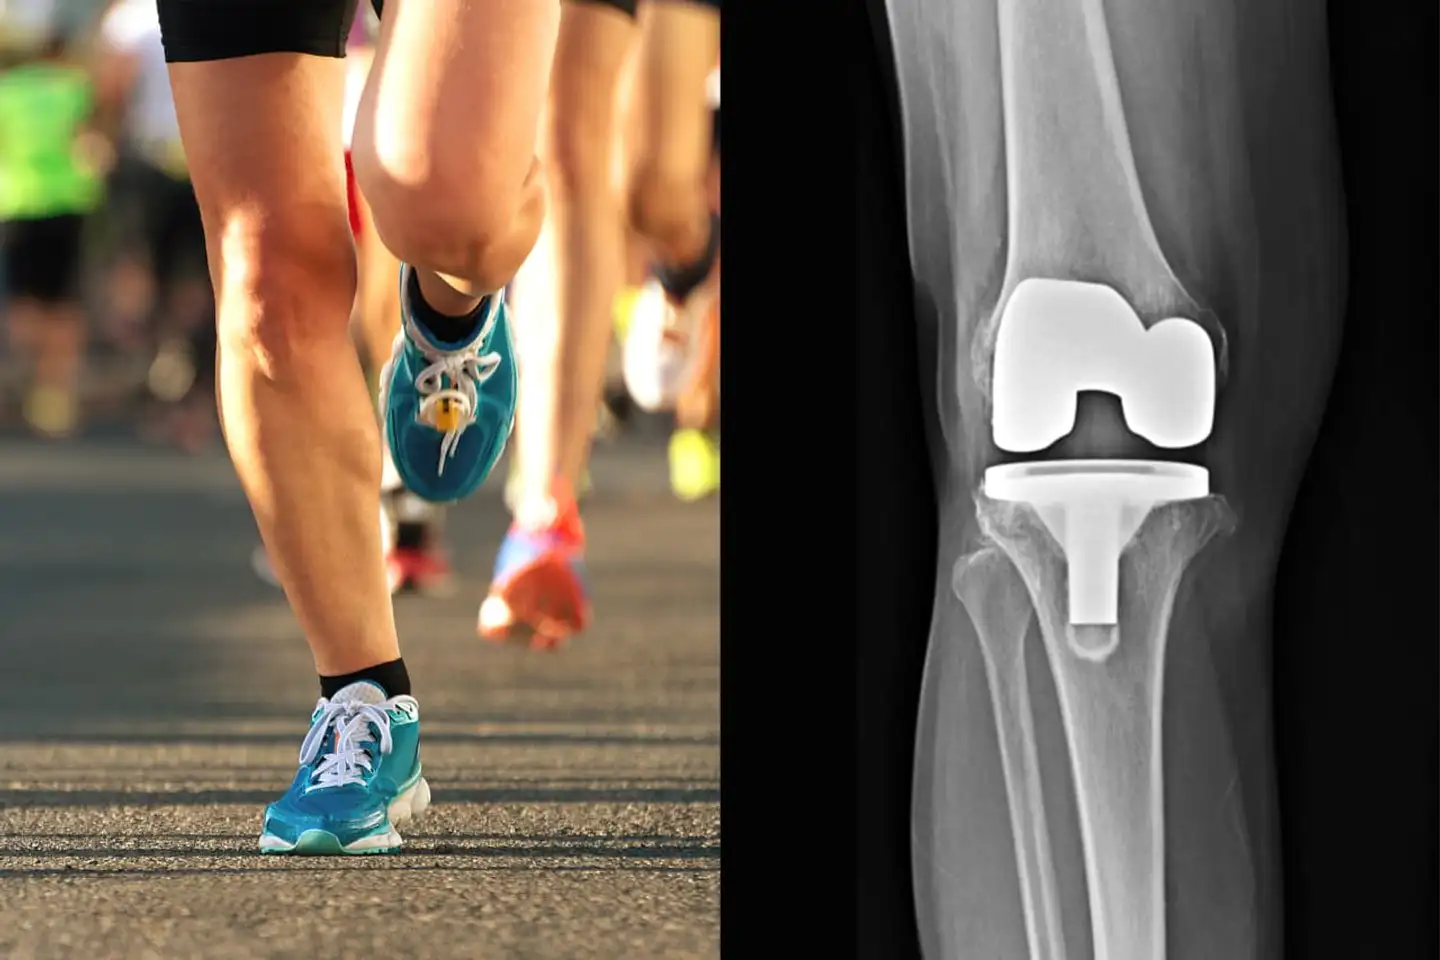

I de to seneste tyve år er antallet af patienter med hofte- eller knæoperationer vokset med 200 procent i USA, viser nye tal. Det er på den ene side fortællingen om, at amerikanerne er blevet mere overvægtige, men det er også historien om, at sundhedsteknologien har gjort store fremskridt, og at folk ikke vil lade sig begrænse som tidligere.

Det kan du læse om her.